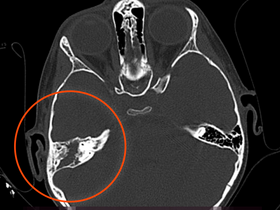

- операції на верхньощелепних пазухах;

- пункція при гаймориті;

В екстреному порядку проводяться операції після травм, у разі сильної носової кровотечі, гострому гаймориті. Дитячий лор-хірург проводить репозицію кісток, тампонади носа, здійснює пункцію для видалення гною з носових пазух.

Для лікування маленьких пацієнтів наші лікарі використовують апарат комп'ютерної томографії з новим програмним забезпеченням, систему моніторингу стану пацієнта під анестезією, мобільну систему моніторингу стану пацієнта від Nihon Kohden (Японія), медичну техніку та інструменти від виробників Stryker, Karl Zeiss, KARL STORZ.